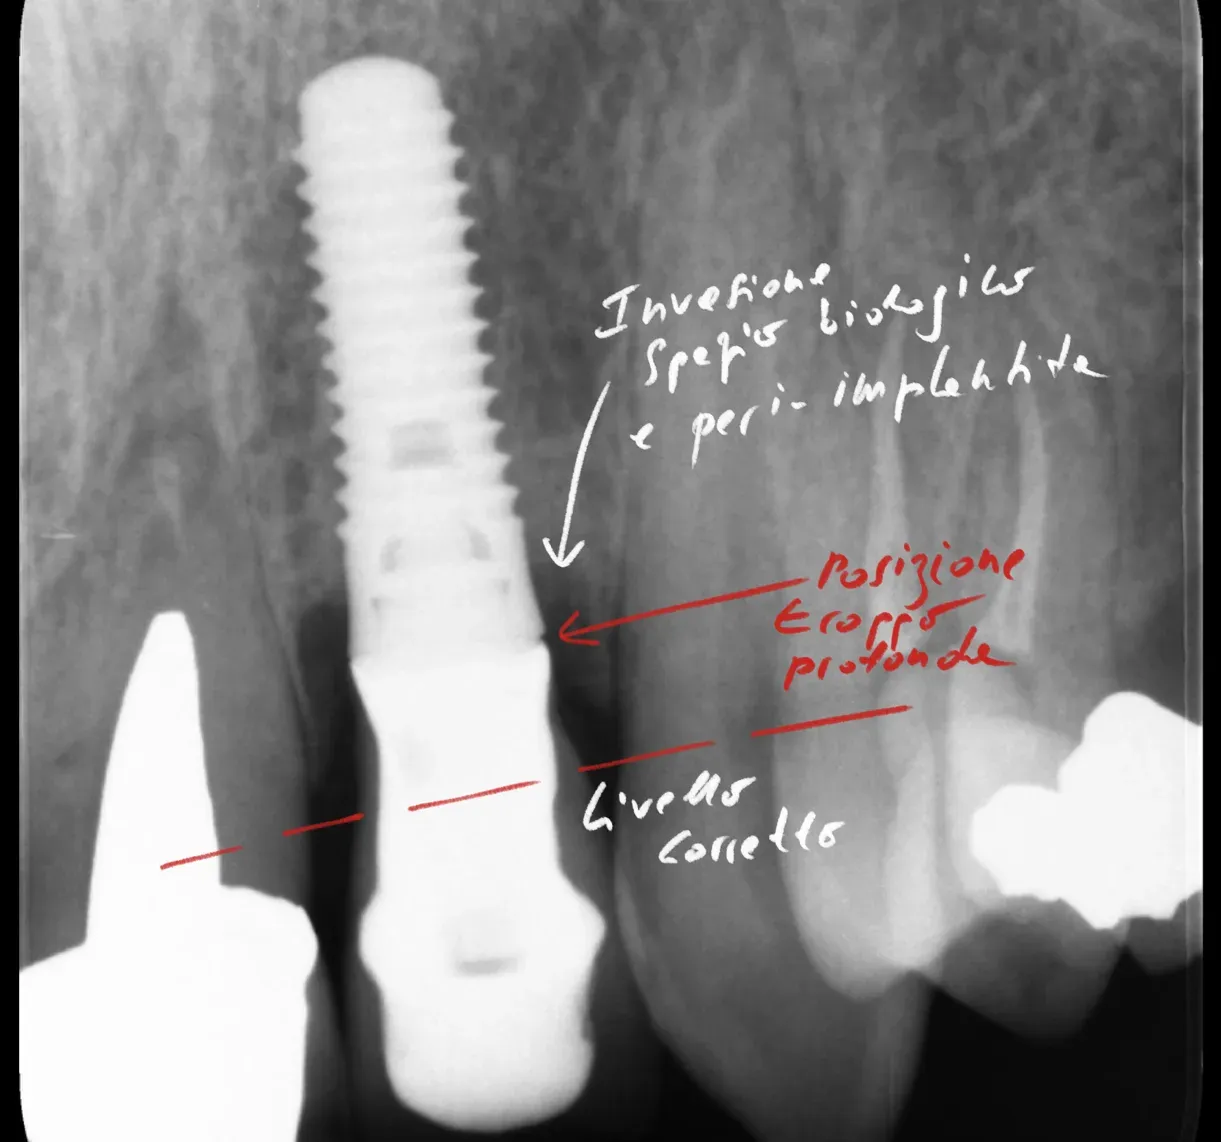

Radiograph of an implant affected by peri-implantitis from incorrect placement